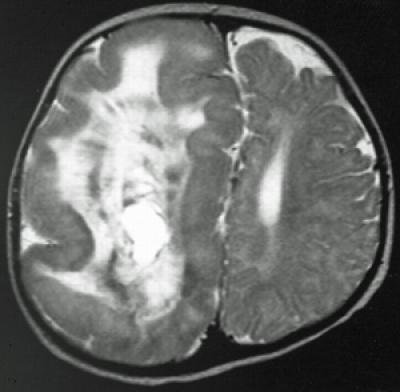

Hemimegalencephaly is a rare but dramatic condition in which the brain grows asymmetrically, with one hemisphere becoming massively enlarged. Though frequently diagnosed in children with severe epilepsy, the cause of hemimegalencephaly is unknown and current treatment is radical: surgical removal of some or all of the diseased half of the brain.

"Although counterintuitive, hemimegalencephaly patients are far better off following the functional removal or disconnection of the enlarged hemisphere," said Mathern. "Prior to the surgery, most patients have devastating epilepsy, with hundreds of seizures per day, completely resistant to even our most powerful anti-seizure medications. The surgery disconnects the affected hemisphere from the rest of the brain, causing the seizures to stop. If performed at a young age and with appropriate rehabilitation, most children suffer less language or cognitive delay due to neural plasticity of the remaining hemisphere."